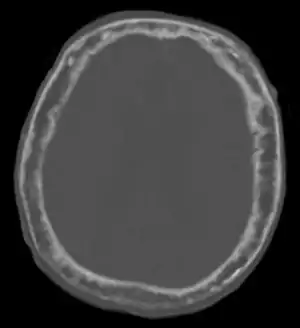

| "This 92 year-old male patient presented for assessment of sudden inability to move half his body. An incidental finding was marked thickening of the calvarium. The diploic space is widened and there are ill-defined sclerotic and lucent areas throughout. The cortex is thickened and irregular. The findings probably correspond to the 'cotton wool spots' seen on plain films in the later stages of Paget’s disease." | |

Paget's disease affecting the skull may cause frontal bossing, increased hat size, and headaches. Often patients may develop loss of hearing in one or both ears[5] due to auditory foramen narrowing and resultant compression of the nerves in the inner ear. Rarely, skull involvement may lead to compression of the nerves that supply the eye, leading to vision loss.[5]

Initially, there is a marked increase in the rate of bone resorption in localized areas, caused by large and numerous osteoclasts. These localized areas of pathological destruction of bone tissue (osteolysis) are seen radiologically as an advancing lytic wedge in long bones or the skull. When this occurs in the skull, it is called osteoporosis circumscripta. The osteolysis is followed by a compensatory increase in bone formation induced by the bone-forming cells, called osteoblasts, that are recruited to the area. This is associated with accelerated deposition of lamellar bone in a disorganized fashion. This intense cellular activity produces a chaotic picture of trabecular bone ("mosaic" pattern), rather than the normal linear lamellar pattern. The resorbed bone is replaced and the marrow spaces are filled by an excess of fibrous connective tissue with a marked increase in blood vessels, causing the bone to become hypervascular. The bone hypercellularity may then diminish, leaving a dense "pagetic bone," also known as burned-out Paget's disease. A later phase of the disease is characterized by the replacement of normal bone marrow with highly vascular fibrous tissue.[25]